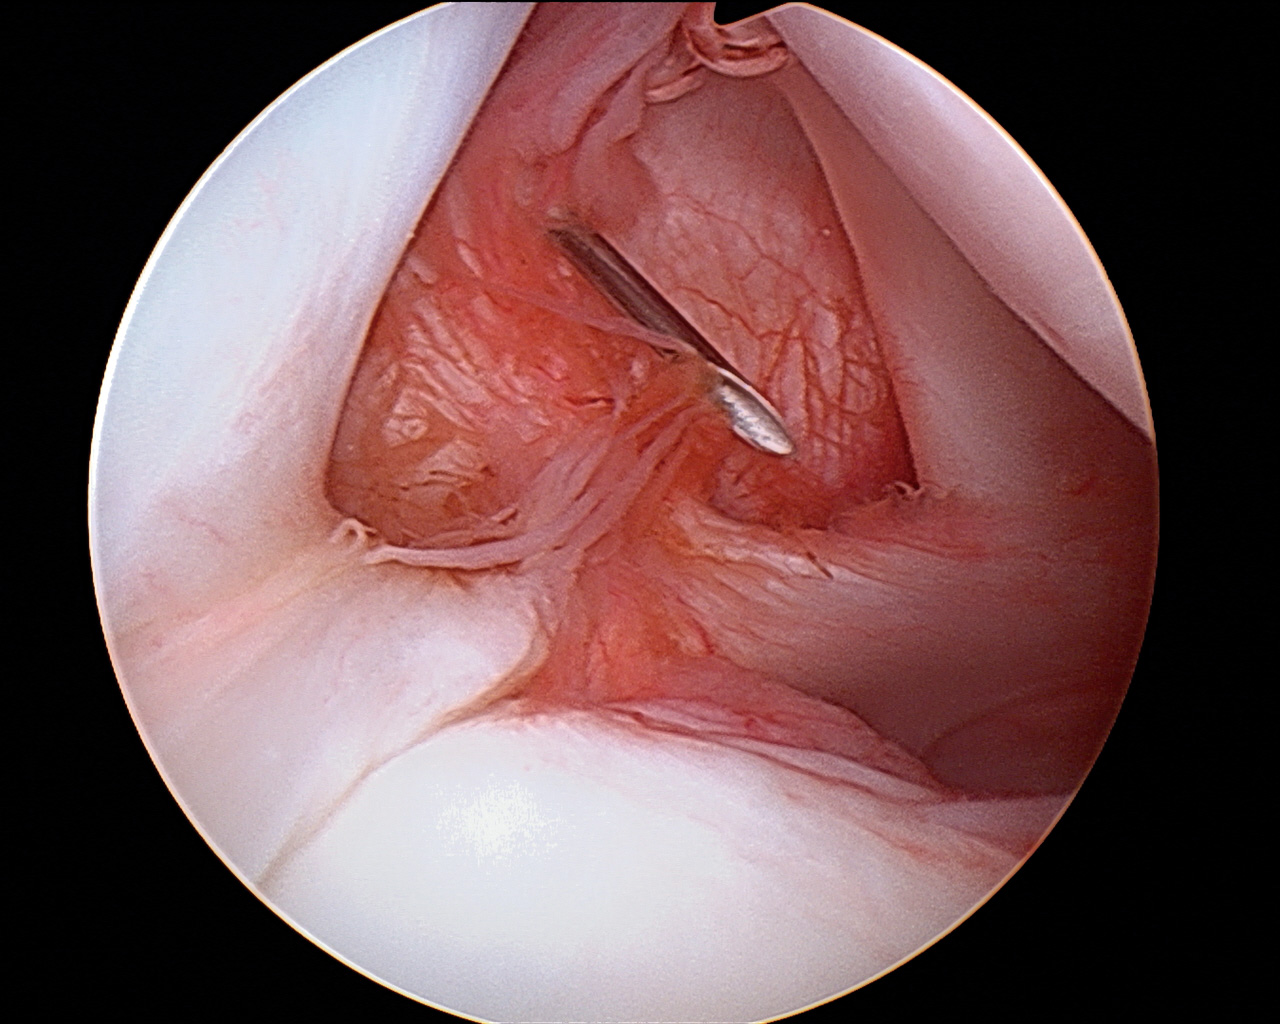

- El pórtico